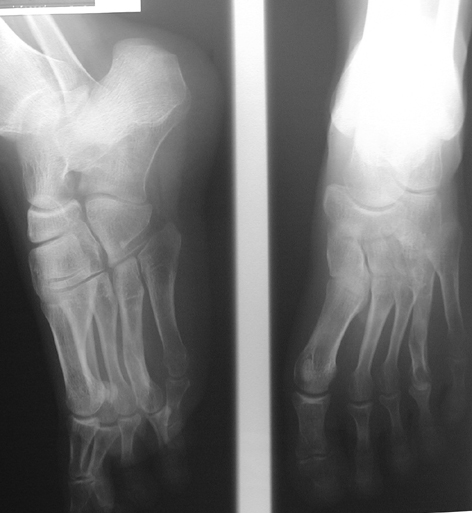

Finger (metacarpus) and toe (metatarsus) shortness can be seen congenitally as a single deformity or as a part of various syndromes; or after trauma or Freiberg disease (avascular necrosis). The frequency of congenital metacarpal or metatarsal shortness is less yhan 1/1000. It is seen 5 times more freqently in women and usually (72%) bilateral. Fourth finger is the most frequently involved. Although the cause of this problem is not known exactly, it is believed that the deformity is usually caused by early closure of the growth plate.

Surgical treatment may be required for metacarpal shortness because of cosmetic disturbance and fatigue in the dominant hand; and for metatarsal shortness because of cosmetic appearance, metatarsalgia, deformity due to dorsal shift of the short finger, pain and pressure ulcers due to plantar shift of the short finger, or difficulty in shoe wearing. Various techniques have been defined for the treatment of congenital metacarpal or metatarsal shortness. However, the most frequently used methods are acute lengthening with grafting, and distraction osteogenesis (callotasis). Callotasis method is preferred for lengthening more than 1 cm. In our department, we prefer distraction osteogenesis with unilateral or circular external fixator for lengthening of metacarpal and metatarsal bones.